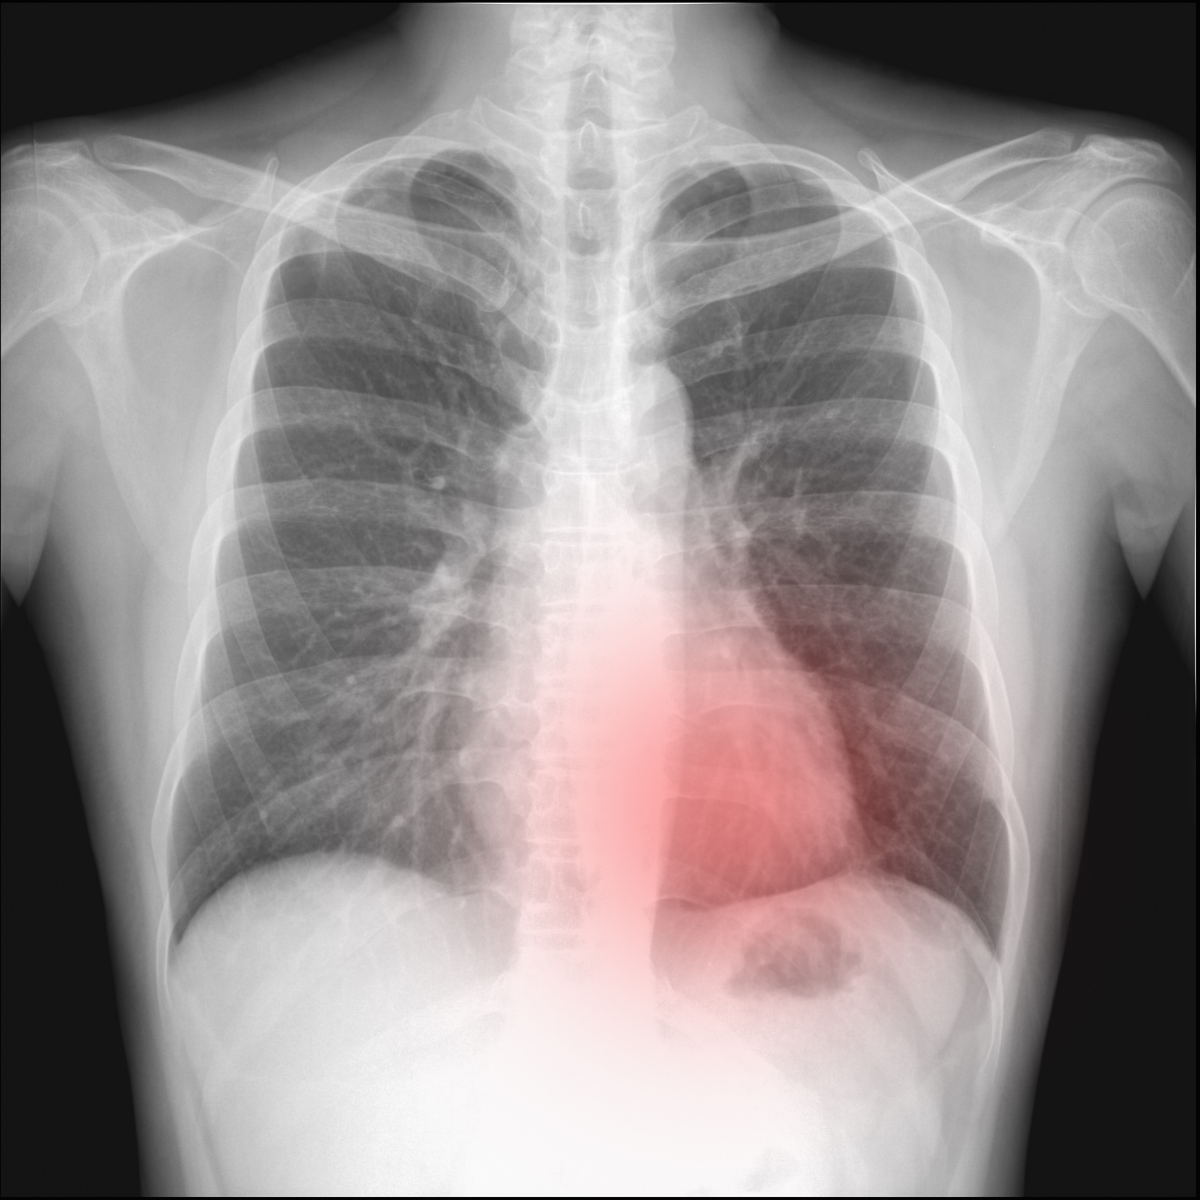

A physical examination will reveal decreased or absent breath sounds on the affected lung on auscultation. Imaging scans such as a chest X-ray or CT scan are used to confirm the diagnosis of pneumothorax.